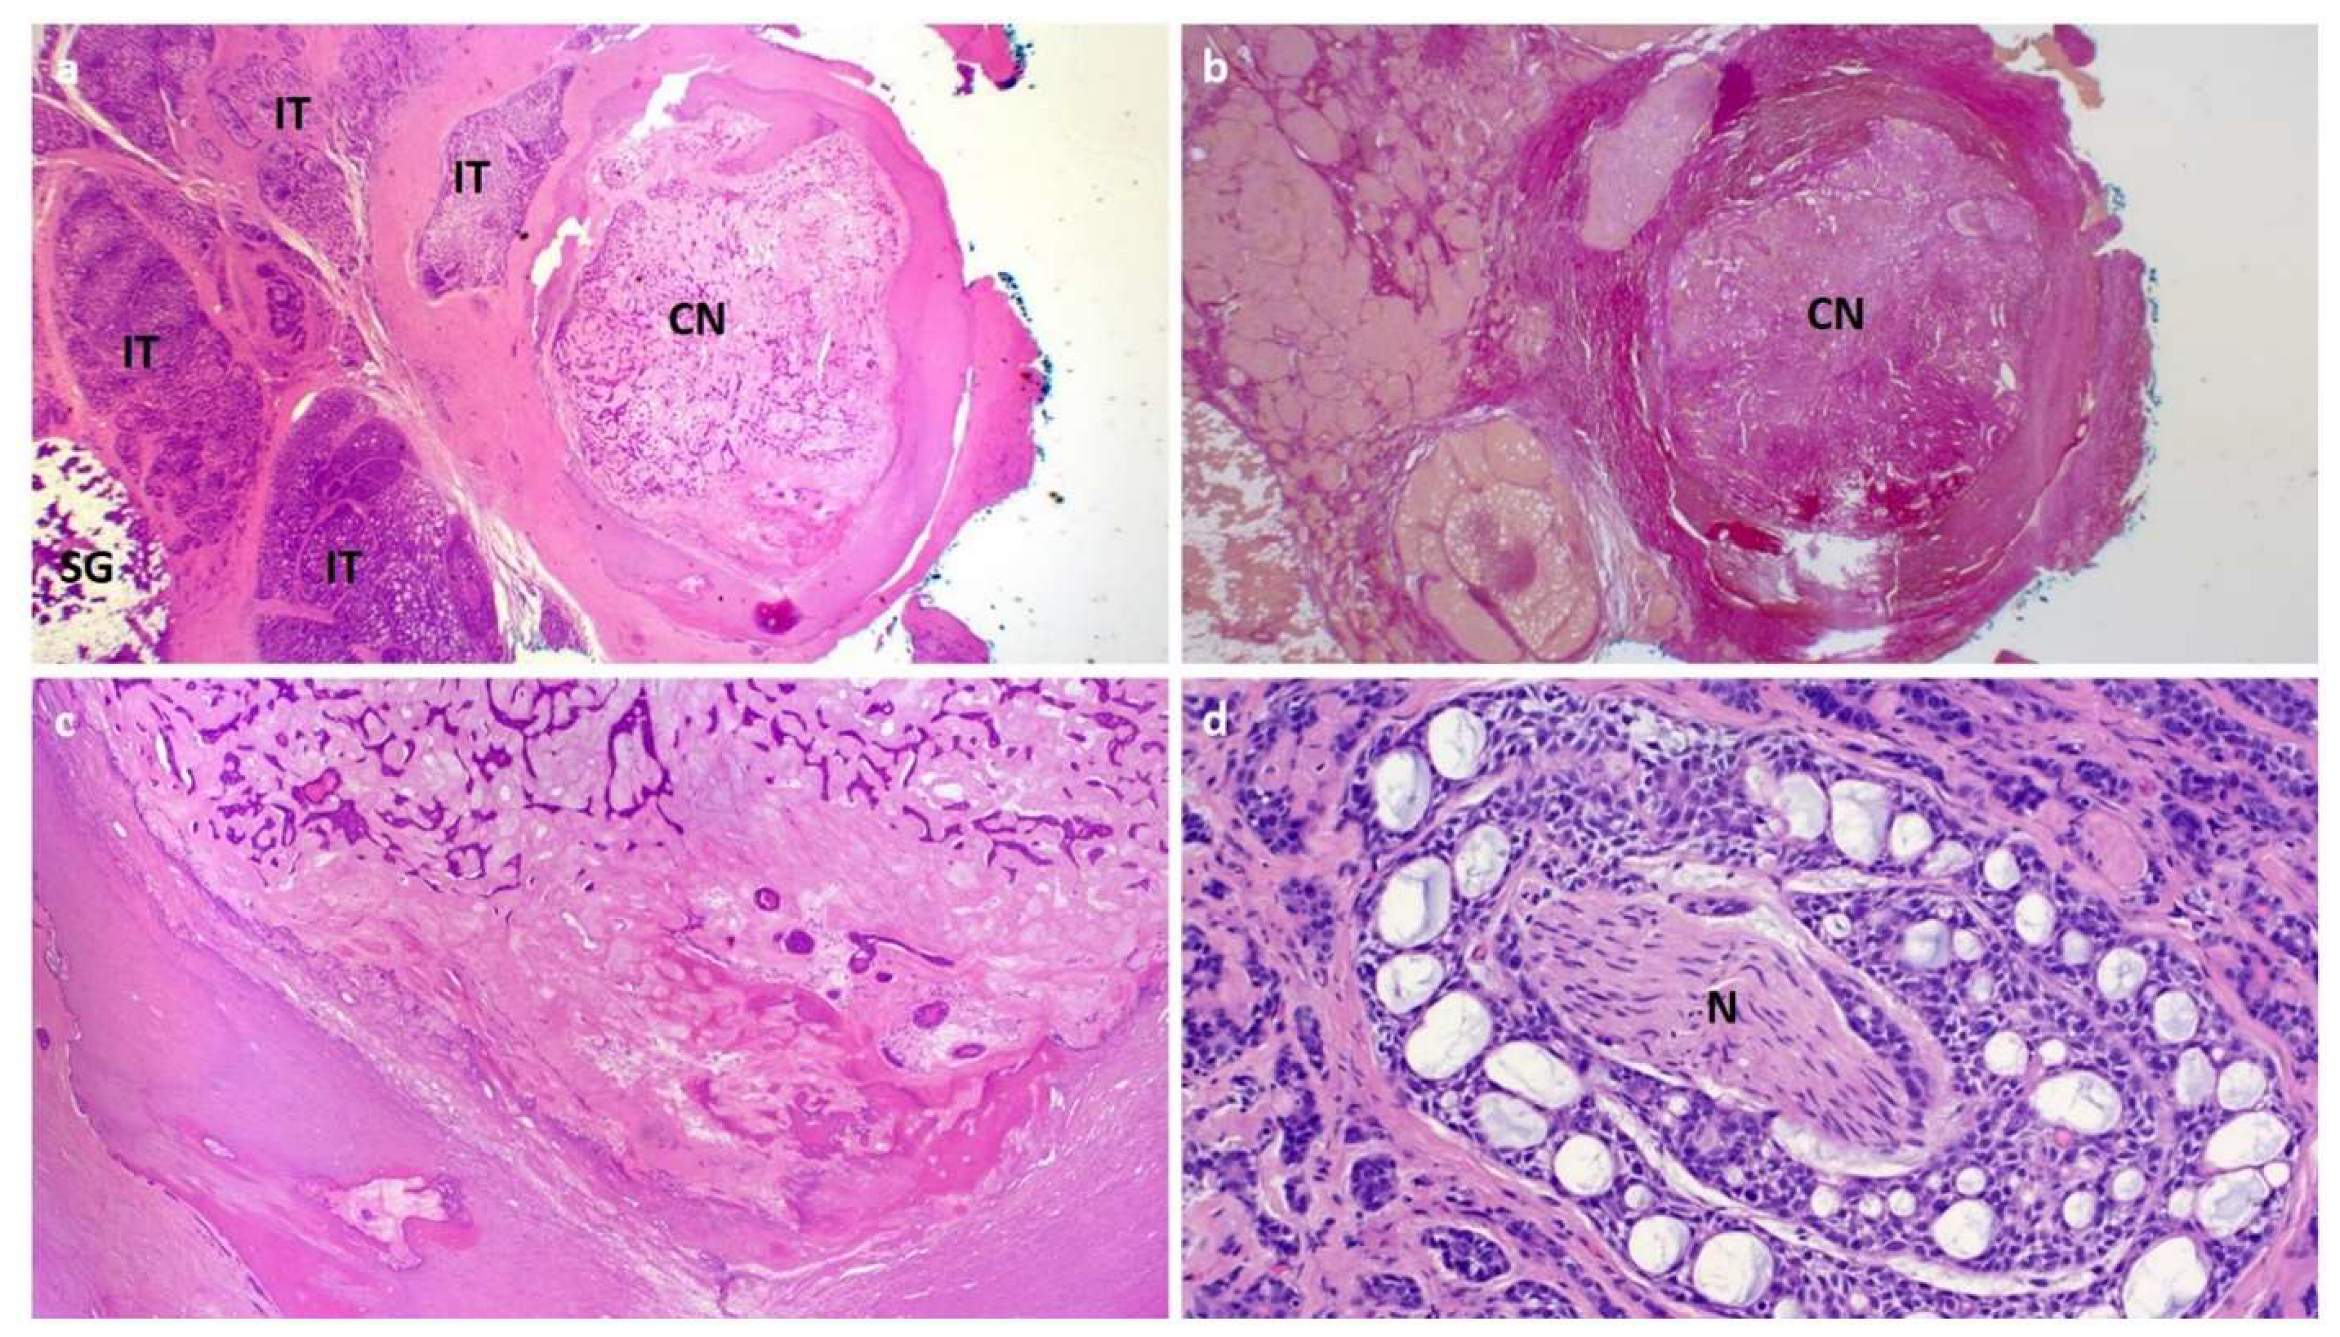

2. Case 1